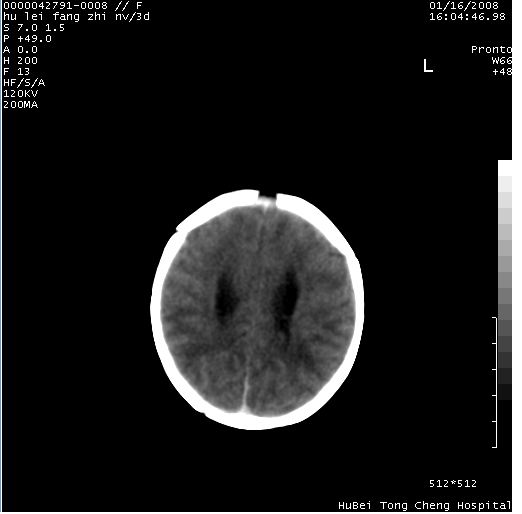

患儿 女,3天。惊跳,纳差。第二胎顺产,羊水ⅱ度。

临床诊断:hie?

颅脑ct轴位平扫(层厚、层距均为7mm),图像如下:

hie合并蛛网膜下腔出血

hie合并蛛网膜下腔出血,五、六脑室形成。

支持hie伴少量蛛血.

支持胼胝体发育不良。

支持hie,胼胝体发育差些

支持胼胝体发育不良